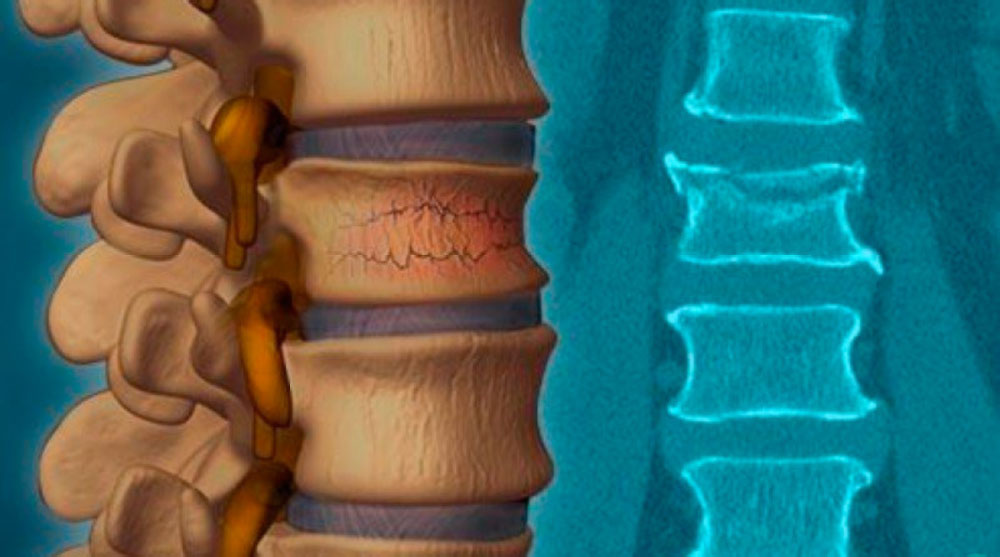

Рентгеновские снимки и медицинские изображения компрессионных переломов